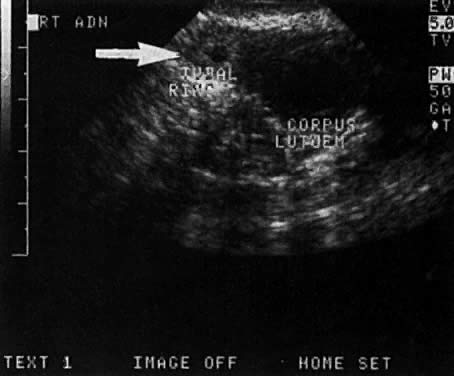

Stovall and associates14 noted a fetal heartbeat in 12% of the ectopic pregnancies, compared to 23% in the study by Timor-Tritsch and colleagues.15 (Fig. 7) A large percentage of the time, identification of an ectopic adnexal mass is based on the findings of a tubal ring or complex adnexal mass (Fig. 8 and Fig. 9). The corpus luteum itself and hemoperitoneum secondary to it can lead to a false-positive diagnosis of ectopic pregnancy. In addition, the clinician should be aware that very small ectopic pregnancies identified on ultrasound may be difficult to identify laparoscopically.

Fig. 9. A 7-mm ectopic tubal ring ( arrow) identified adjacent to a larger cystic corpus luteum.